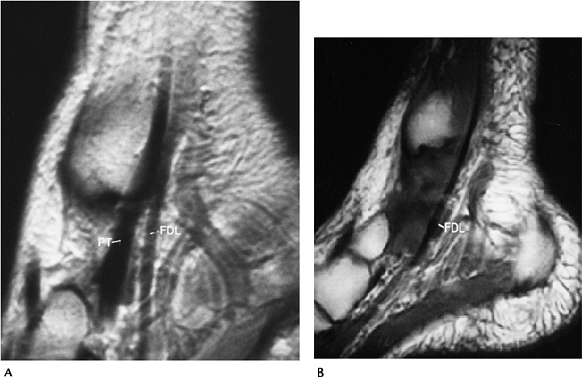

Soft Tissue Trauma/Overuse Syndromes: Medial Tendon Injuries

-

From anterior to posterior, the medial

tendons include the tibialis posterior, flexor digitorum longus, and

flexor hallucis longus. -

Abnormalities in the medial tendons include degeneration, partial and complete tears, and subluxation or dislocation.

Tibialis posterior tendon disorders are

most common. Patients usually are middle-aged or older females with

ankle pain, instability, and foot deformities. -

More than 50% have abnormalities on routine radiographs.

Feature Incidence ↓ Calcaneal inclination 50% ↑ Lateral talometatarsal angle 47% ↑ Anterior talocalcaneal angle 43% Medial swelling 27% Accessory navicular 17% -

There are three types of accessory

navicular. Type I: oval, imbedded in tendon. Type II: triangular with

fibrocartilaginous synchondrosis. Type III: cornuate and incompletely

incorporated into the navicular. Types II and III: associated with

posterior tibial tendon dysfunction. -

Flexor digitorum longus and flexor

hallucis longus tenosynovitis occur and may be seen in ballet dancers

and soccer players. Rupture of these tendons is uncommon. -

MRI is the technique of choice. Axial and sagittal T2-weighted images define the type and extent of injury.

![]() |

|

FIGURE 6-50 MRI of a posterior tibial tendon tear. (A) Normal sagittal image with posterior tibial (PT) and flexor digitorum longus (FDL) tendons clearly demonstrated. (B)

Sagittal proton density image showing the flexor digitorum longus (FDL) with no posterior tibial tendon because of a complete tear with retraction. |